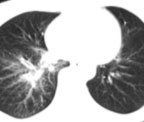

慢性支氣管炎主要表現為每年發作至少三個月,並持續2年或2年以上的咳嗽、咯痰或氣喘等。但要注意除外其他伴有上述症狀的心肺疾病,如肺纖維化等。由於慢性氣管炎多緩慢起病,病程較長,且經反覆急性發作而加重。慢性支氣管炎初期,緩解期可無症狀,但在每年冬季都會發病好幾次。到了慢性支氣管炎的末期,咳嗽、咯痰及呼吸困難等症狀,幾乎是終年不停的。